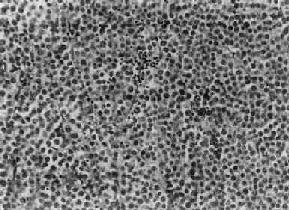

图14-1 精原细胞

细胞大、胞浆透明,核大,核仁明显,间质内有淋巴细胞浸润

肉眼观,睾丸肿大,有时可达正常体积的10倍,少数病例睾丸大小正常。肿体积大小不一,小者仅数毫米,大者可达十余厘米,通常直径为3~5cm。由于睾丸白膜比较韧厚,未被肿破坏,故通常睾丸的原来轮廓尚保存。切面组织呈淡黄或灰黄色,实体性,均匀一致如鱼肉,其中往往可见到不规则坏死区。镜下,典型的精原细胞细胞形态结构单一和间质内有淋巴细胞浸润两个特征,(图14-1)。细胞弥漫分布或呈索状结构,细胞的形态一致,与正常精小管内精原细胞相似,细胞大,圆形或多角形、境界清楚、胞浆透明,核大、位于中央,核膜及染色质较粗,有1~2个嗜酸性核仁,核分裂像不多见。间质为纤细的纤维组织或致密的胶原纤维,其中有多少不等的淋巴细胞浸润,有时可有淋巴滤泡形成。